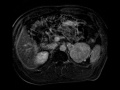

Paraganglioma

MR images demonstrate a T1 hypointense, T2 hyperintense, avidly enhancing mass in the left upper quadrant, found to be separate from the adjacent left adrenal gland. This was found to represent extra-adrenal paraganglioma